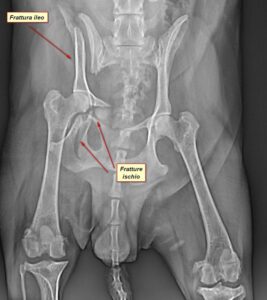

Ortopedia e traumatologia veterinaria a bologna

L’ortopedia veterinaria ha subito negli ultimi 15 anni una vera e propria rivoluzione.

Si è passati da concetti già avanzati di guarigione biologica delle fratture ai concetti di biomeccanica più recenti, ove le patologie vengono studiate tracciando linee e calcolando angoli su immagini a risoluzione sempre più elevata.

Ne sono un esempio l’approccio attuale alle patologie del ginocchio, alle deformazioni scheletriche in fase di crescita (deviazioni angolari/assiali) e alla displasia dell’anca, così come il recente utilizzo dei sistemi di sintesi in titanio a stabilità angolare per le fratture complesse o le osteotomie correttive.

Si eseguono interventi di:

- tplo – rottura del legamento crociato

- tpo – per displasia dell’anca

- riparazioni chirurgiche per fratture (comminuta distale del femore, gomito intercondilare, fratture del bacino, tibiali, femorali ecc)

- chirurgie correttive per patologie di accrescimento (torsione della tibia del cane, deviazione laterale della mano

- lussazioni sacroiliache.

Inoltre, si effettuano intervento in artroscopia (chirurgia mini invasiva artroscopica).

Nella gallery qui sotto alcuni dei nostri casi clinici.